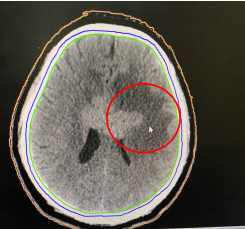

已经步入中年的刘先生,饱受颅内淋巴瘤晚期的折磨。今年三月份,全国正处在新冠疫情攻坚战时期,许多医院放射治疗科采取了闭诊举措。就在那个社会恐慌、正常医疗资源紧张的关口,刘先生一家来到了在疫情期仍然坚持接诊的清华大学附属北京清华长庚医院放射治疗科就诊。科主任黎功对接诊的场景至今记忆犹新,躺在担架床上的患者已出现意识模糊,自主行动能力丧失,大小便失禁等症状,情况不乐观。经评估,黎功为患者采取了“放疗+免疫”的治疗疗法,即进行放射治疗的同时,采用最新的免疫药物联合治疗。经过几个疗程治疗后,刘先生不仅恢复了自主行动能力,经影像学检查,患者颅内的淋巴瘤也已消失,达到了康复的标准。

治疗前(红色区域为肿瘤)                治疗后5个月肿瘤消失